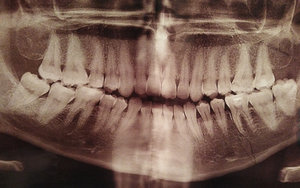

На каких зубах существует вероятность пульпита? 2. Есть ли вероятность, что на снимке присутствуют зубы, такие, что зуб значительно разрушен (от четырёх поверхностей), поэтому здесь требуется восстановление. То есть речь идёт о ситуации кариеса, когда пострадало более трёх поверхностей. Как известно, любой зуб имеет пять поверхностей (1. С внешней стороны. 2. С внутренней стороны (со стороны языка). 3. Со стороны левого соседнего зуба. 4. Со стороны правого соседнего зуба. 5. С жевательной стороны. Я понимаю, что точно диагноз нельзя поставить только по снимку, потому что нужен и визуальный осмотр, но речь идёт просто о возможности (подозрительных зубах и наиболее сложных).

Прям четких пульпитных явлений на снимке я не увидел. Шестой зуб сверху (26), требует установки коронки из-за большого количества пломбы, что по показаниям требуется реставрация вкладкой и коронкой. Не знаю про какой зуб идёт речь, но при разрушении коронковой части зуба более, чем на 50%, необходимо устанавливать коронки. Для более подробной консультации, обратитесь к стоматологу на очный приём.